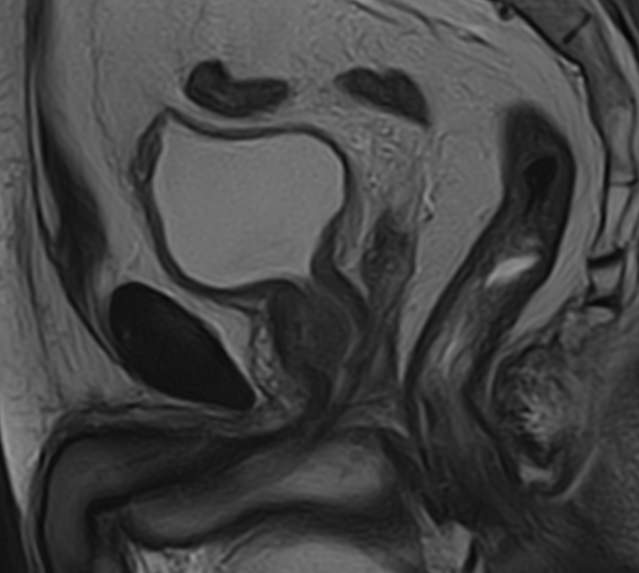

Простата расположена в труднодоступной для диагностики анатомической области, однако метод магнитно-резонансной томографии позволяет детально изучить структуру органа и окружающих ее тканей, включая семенные пузырьки (секреторные органы, вырабатывающие жидкую часть семенной жидкости) и семявыносящие протоки.

В клинике «Доступная медицина» диагностика заболеваний предстательной железы на экспертном уровне выполняется при помощи современного высокопольного магнитно-резонансного томографа TOSHIBA VANTAGE TITAN 1,5 Тесла. Аппарат производит сканирование в виде послойных тонких срезов с шагом от 1 мм и преобразует их при помощи новейших цифровых программ в изображения трехмерного формата. Методика позволяет получить максимально полную картину о состоянии структуры простаты и окружающих тканей и поставить точный диагноз.